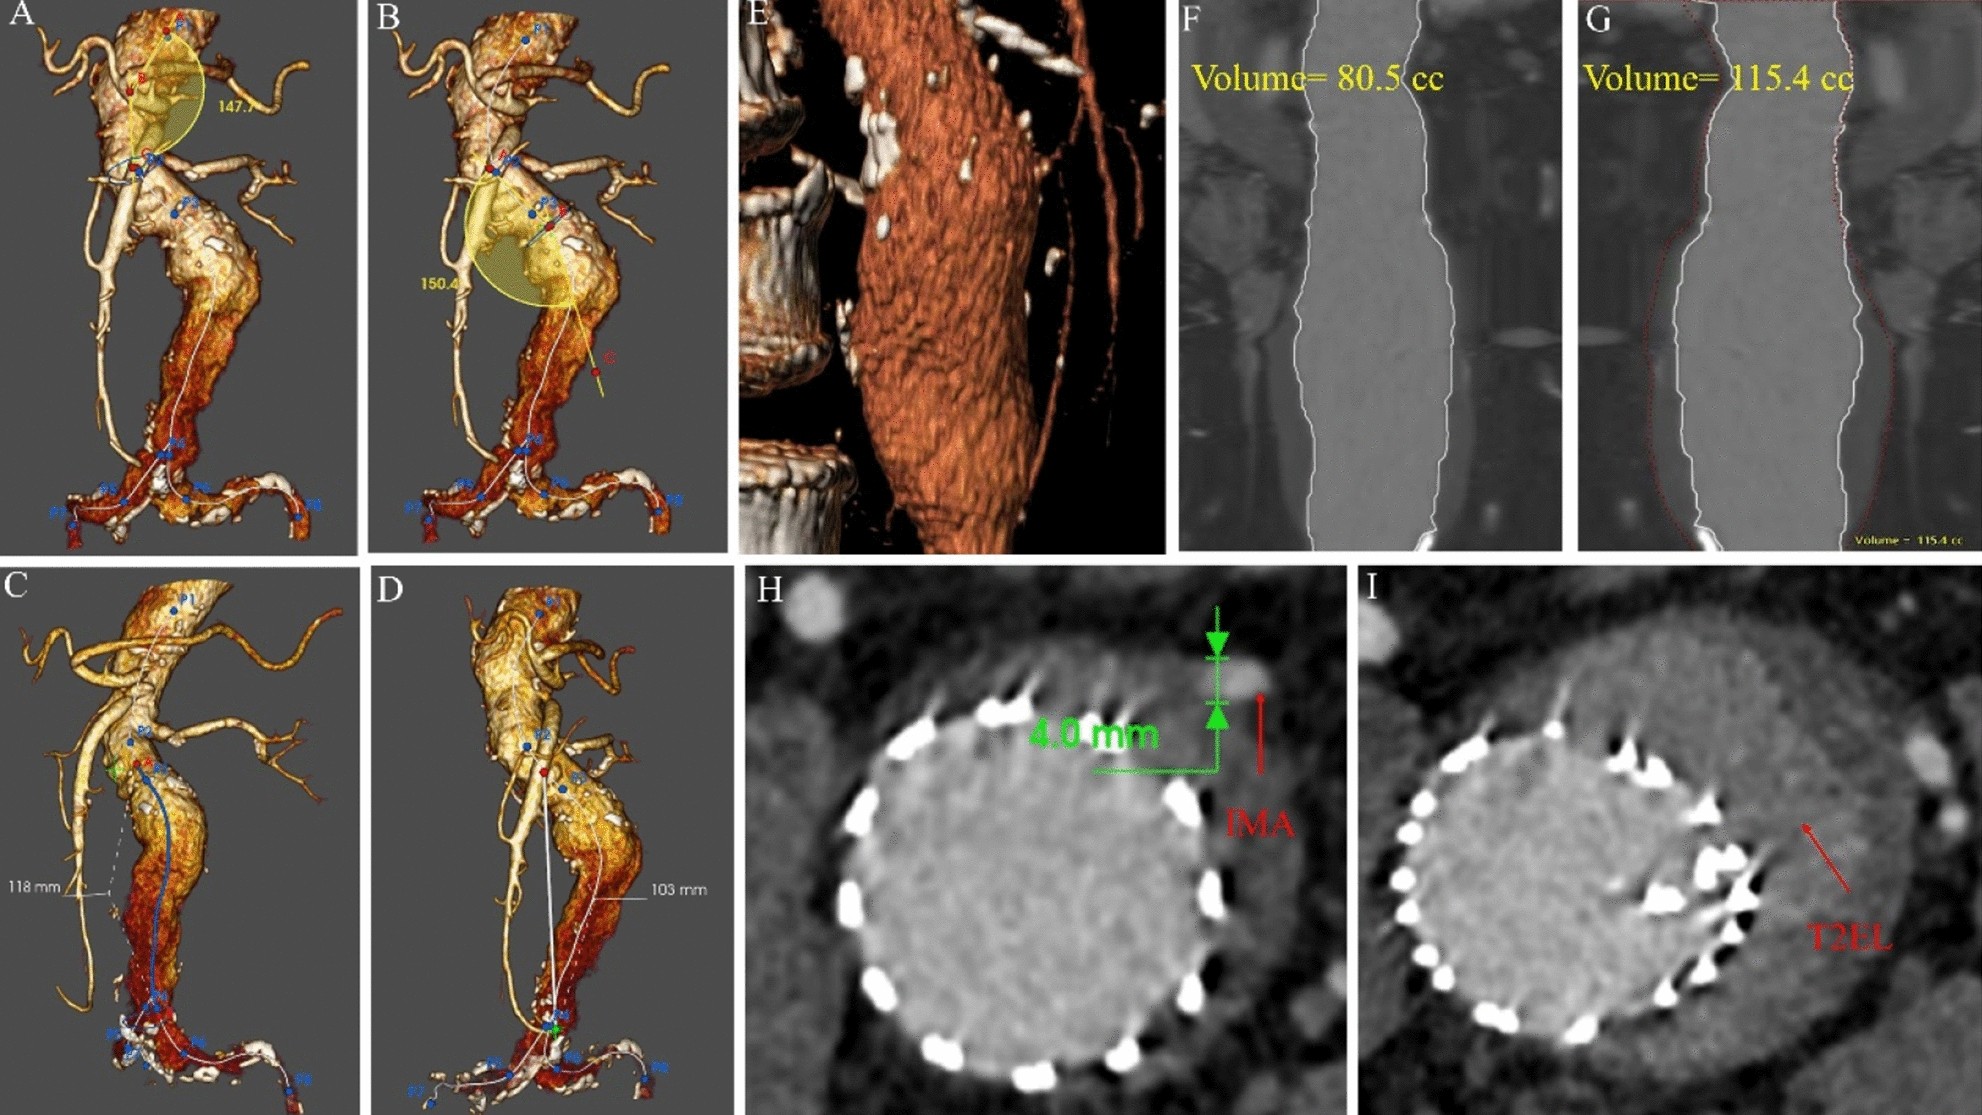

Figure 2

The morphological features of abdominal aortic aneurysm. (A) Angle (α) is defined as the angle between the central line of the upper abdominal aorta of the kidney and the central line of the lower abdominal aortic aneurysm neck. (B) Angle (β) is the angle between the aneurysm neck and the centerline of the aneurysm body. (C) L1 is defined as the length of the central line of the aneurysm. (D) L2 is defined as the length of the distance at the beginning to the end of the aneurysm. (E) The three-dimensional reconstruction of aneurysm sac by 3-Mensio software for estimating the proportion of thrombus. (F) The volume of blood in the aneurysm sac. (G) The volume of the whole aneurysm sac. (H) The diameter of the inferior mesenteric artery was measured by Endosize. (I) The occurrence of T2EL was identified by CTA.